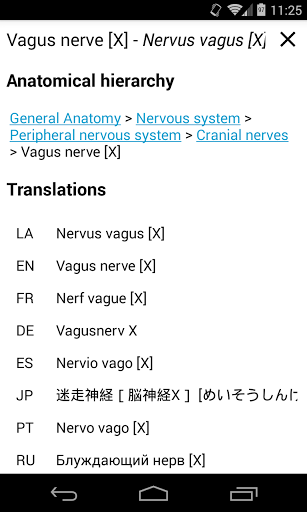

e-Anatomy tiene más de 26 000 imágenes que contienen series de imágenes en vistas axiales, coronales y sagitales, así como radiografías, angiografías, imágenes de disección, gráficos anatómicos e ilustraciones. Todas las imágenes médicas fueron etiquetadas cuidadosamente, más de 967 000 etiquetas disponibles en 12 idiomas, incluida la Terminologia Anatomica latina.

- Cambie de idioma con solo tocar un botón

. *Navegación entre partes anatómicas usando enlaces de descripción.